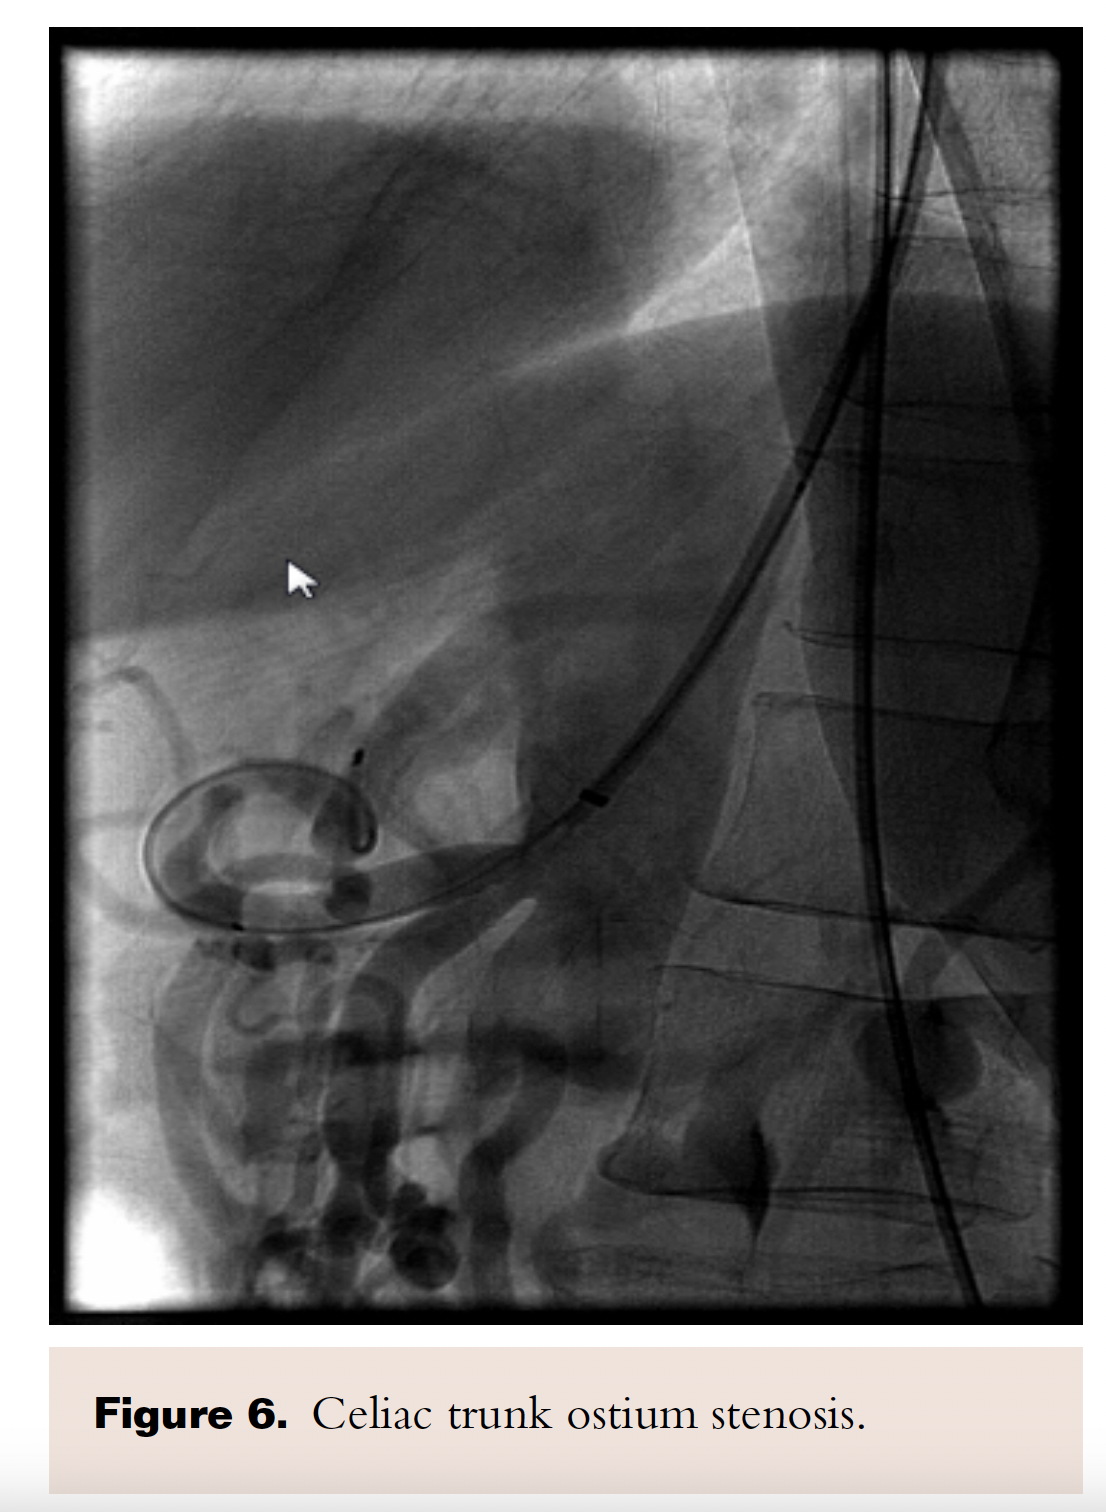

PTA of the proximal celiac trunk was performed with a 6.0 x 20 mm Mustang balloon. As expected, there was no significant angiographic improvement post balloon dilatation (Figure 6). A 6.0 x 16 mm Atrium stent was deployed across the target lesion at 12 atm. There was 0% stenosis post stent placement (Figure 7).